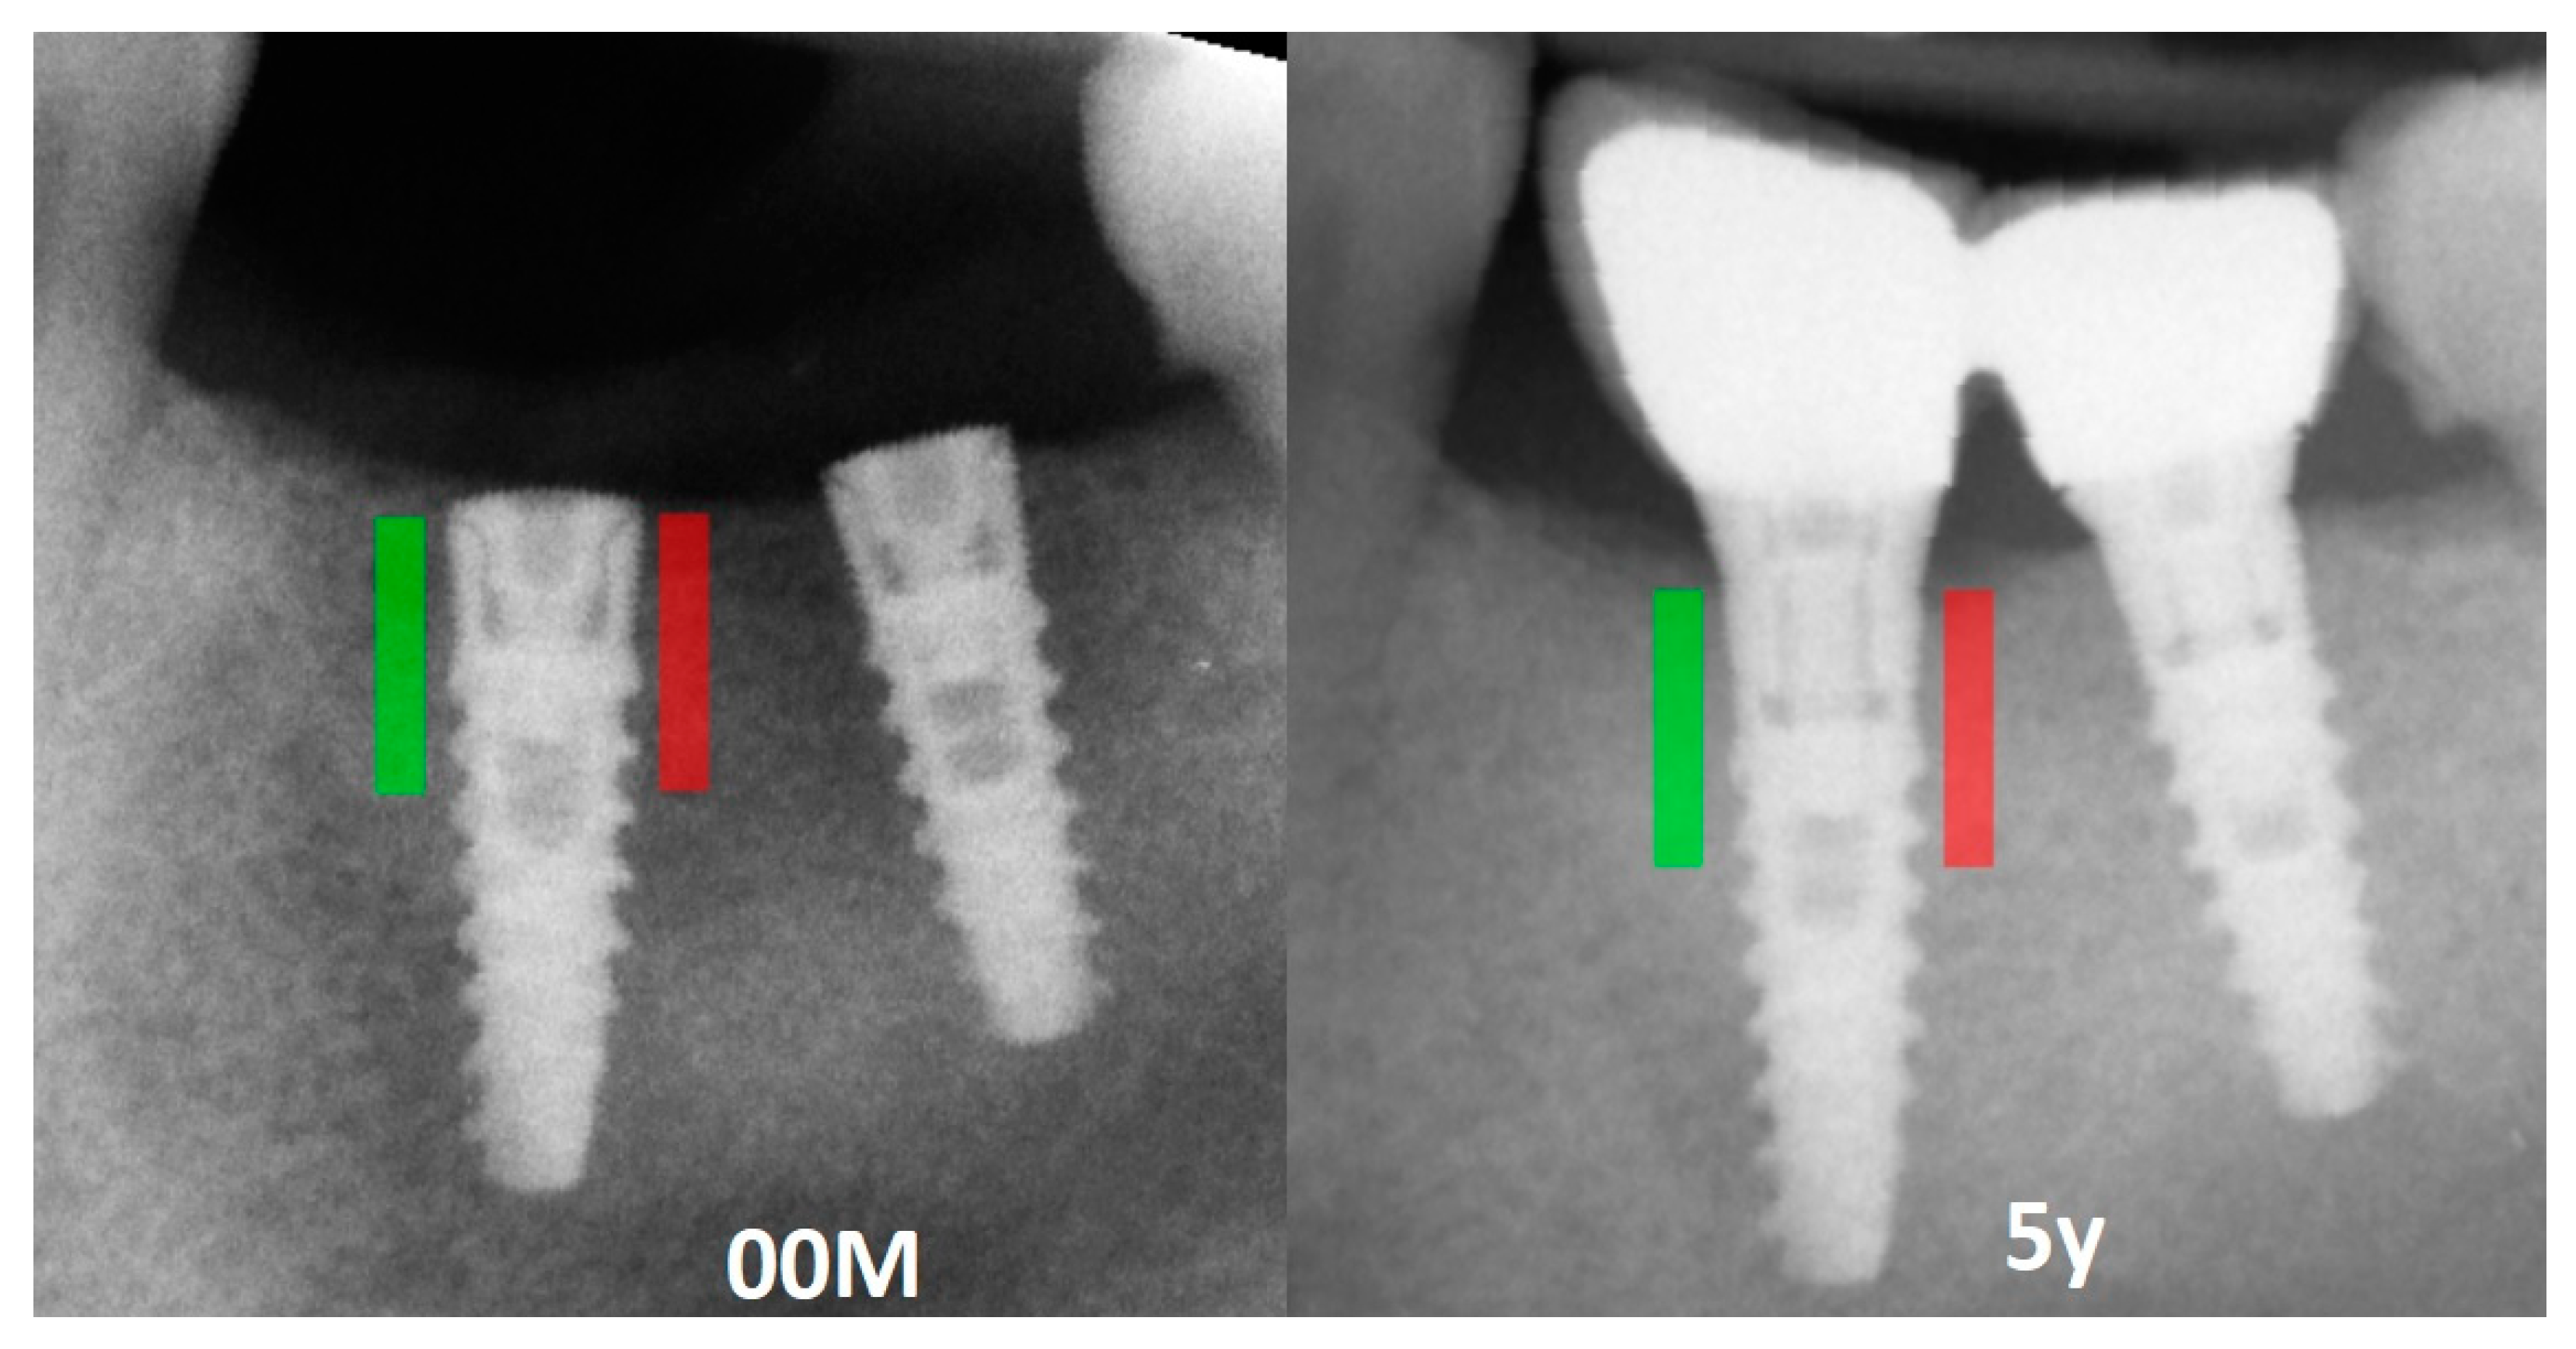

Figure 2.

Marking an ROI. ROIs were marked near the implant neck area. Green area—mesial implant neck area; red area—distal implant neck area; Abbreviations: ROI—region of interest; 00M—0 months of observation; 5y—five years of observation.